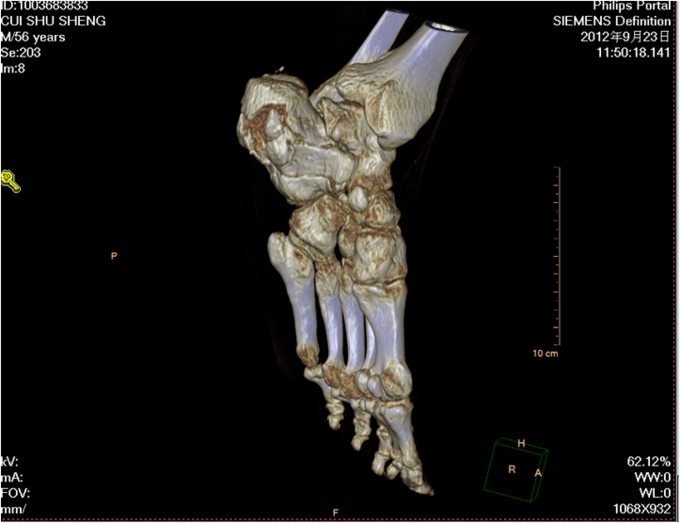

主 诉:摔伤左足跟部疼痛活动受限1小时。现病史:1小时前在自家干活时不慎从2米高梯子上摔下,当时患者意识清醒,无法站立,左踝部疼痛、肿胀、活动受限;被急送往中国医科大学附属盛京医院,经急诊医师会诊后,建议住院治疗,患者及其家属今为进一步治疗,要求入院,我科以“左踝部骨折”为诊断收入我科;患者伤来无发热、无头晕、恶心呕吐,无呼吸困难,既往饮食睡眠可,大小便正常;

左踝部肿胀明显,压痛阳性,左踝部活动受限,可闻及骨擦音及骨擦感;患肢皮肤感觉较健侧无明显异常,足趾可活动,足背动脉可触及; 望:神志清,精神尚可,面色微黄,营养良好,体型中等,舌红,苔薄黄;闻:语声重浊,呼吸均匀,未闻及特殊气味;切:脉弦紧。

中医诊断:左跟骨粉碎骨折(气滞血瘀) 西医诊断:左跟骨粉碎骨折 治疗:手术治疗 中医辨证论治:根据骨伤科三期辨证理论,早期因瘀血停滞影响骨痂生长,故以活血化瘀,消肿止痛为主,应用桃红四物汤;中后期补益肝肾,补气养血,应用愈骨胶囊等药物应用。现患者属于骨折早期,可运用桃红四物汤加减对症治疗,方药如下: 桃仁10g 红花10g 当归12g 川芎12g 赤芍12g 穿山甲6g 柴胡12g 黄芩10g 香附12g 延胡索15g 续断15g 生地12g 甘草6g 3剂 用法:每日一剂,水煎服400ml,分早晚两次温服。 中医调护:避风寒,慎起居,忌生冷,畅情志。